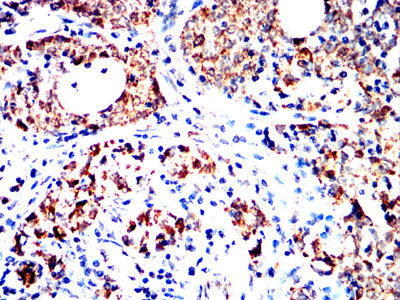

Immunohistochemical analysis of paraffin-embedded human cervical cancer tissues using XPC mouse mAb with DAB staining.

Immunohistochemical analysis of paraffin-embedded human ovarian cancer tissues using XPC mouse mAb with DAB staining.